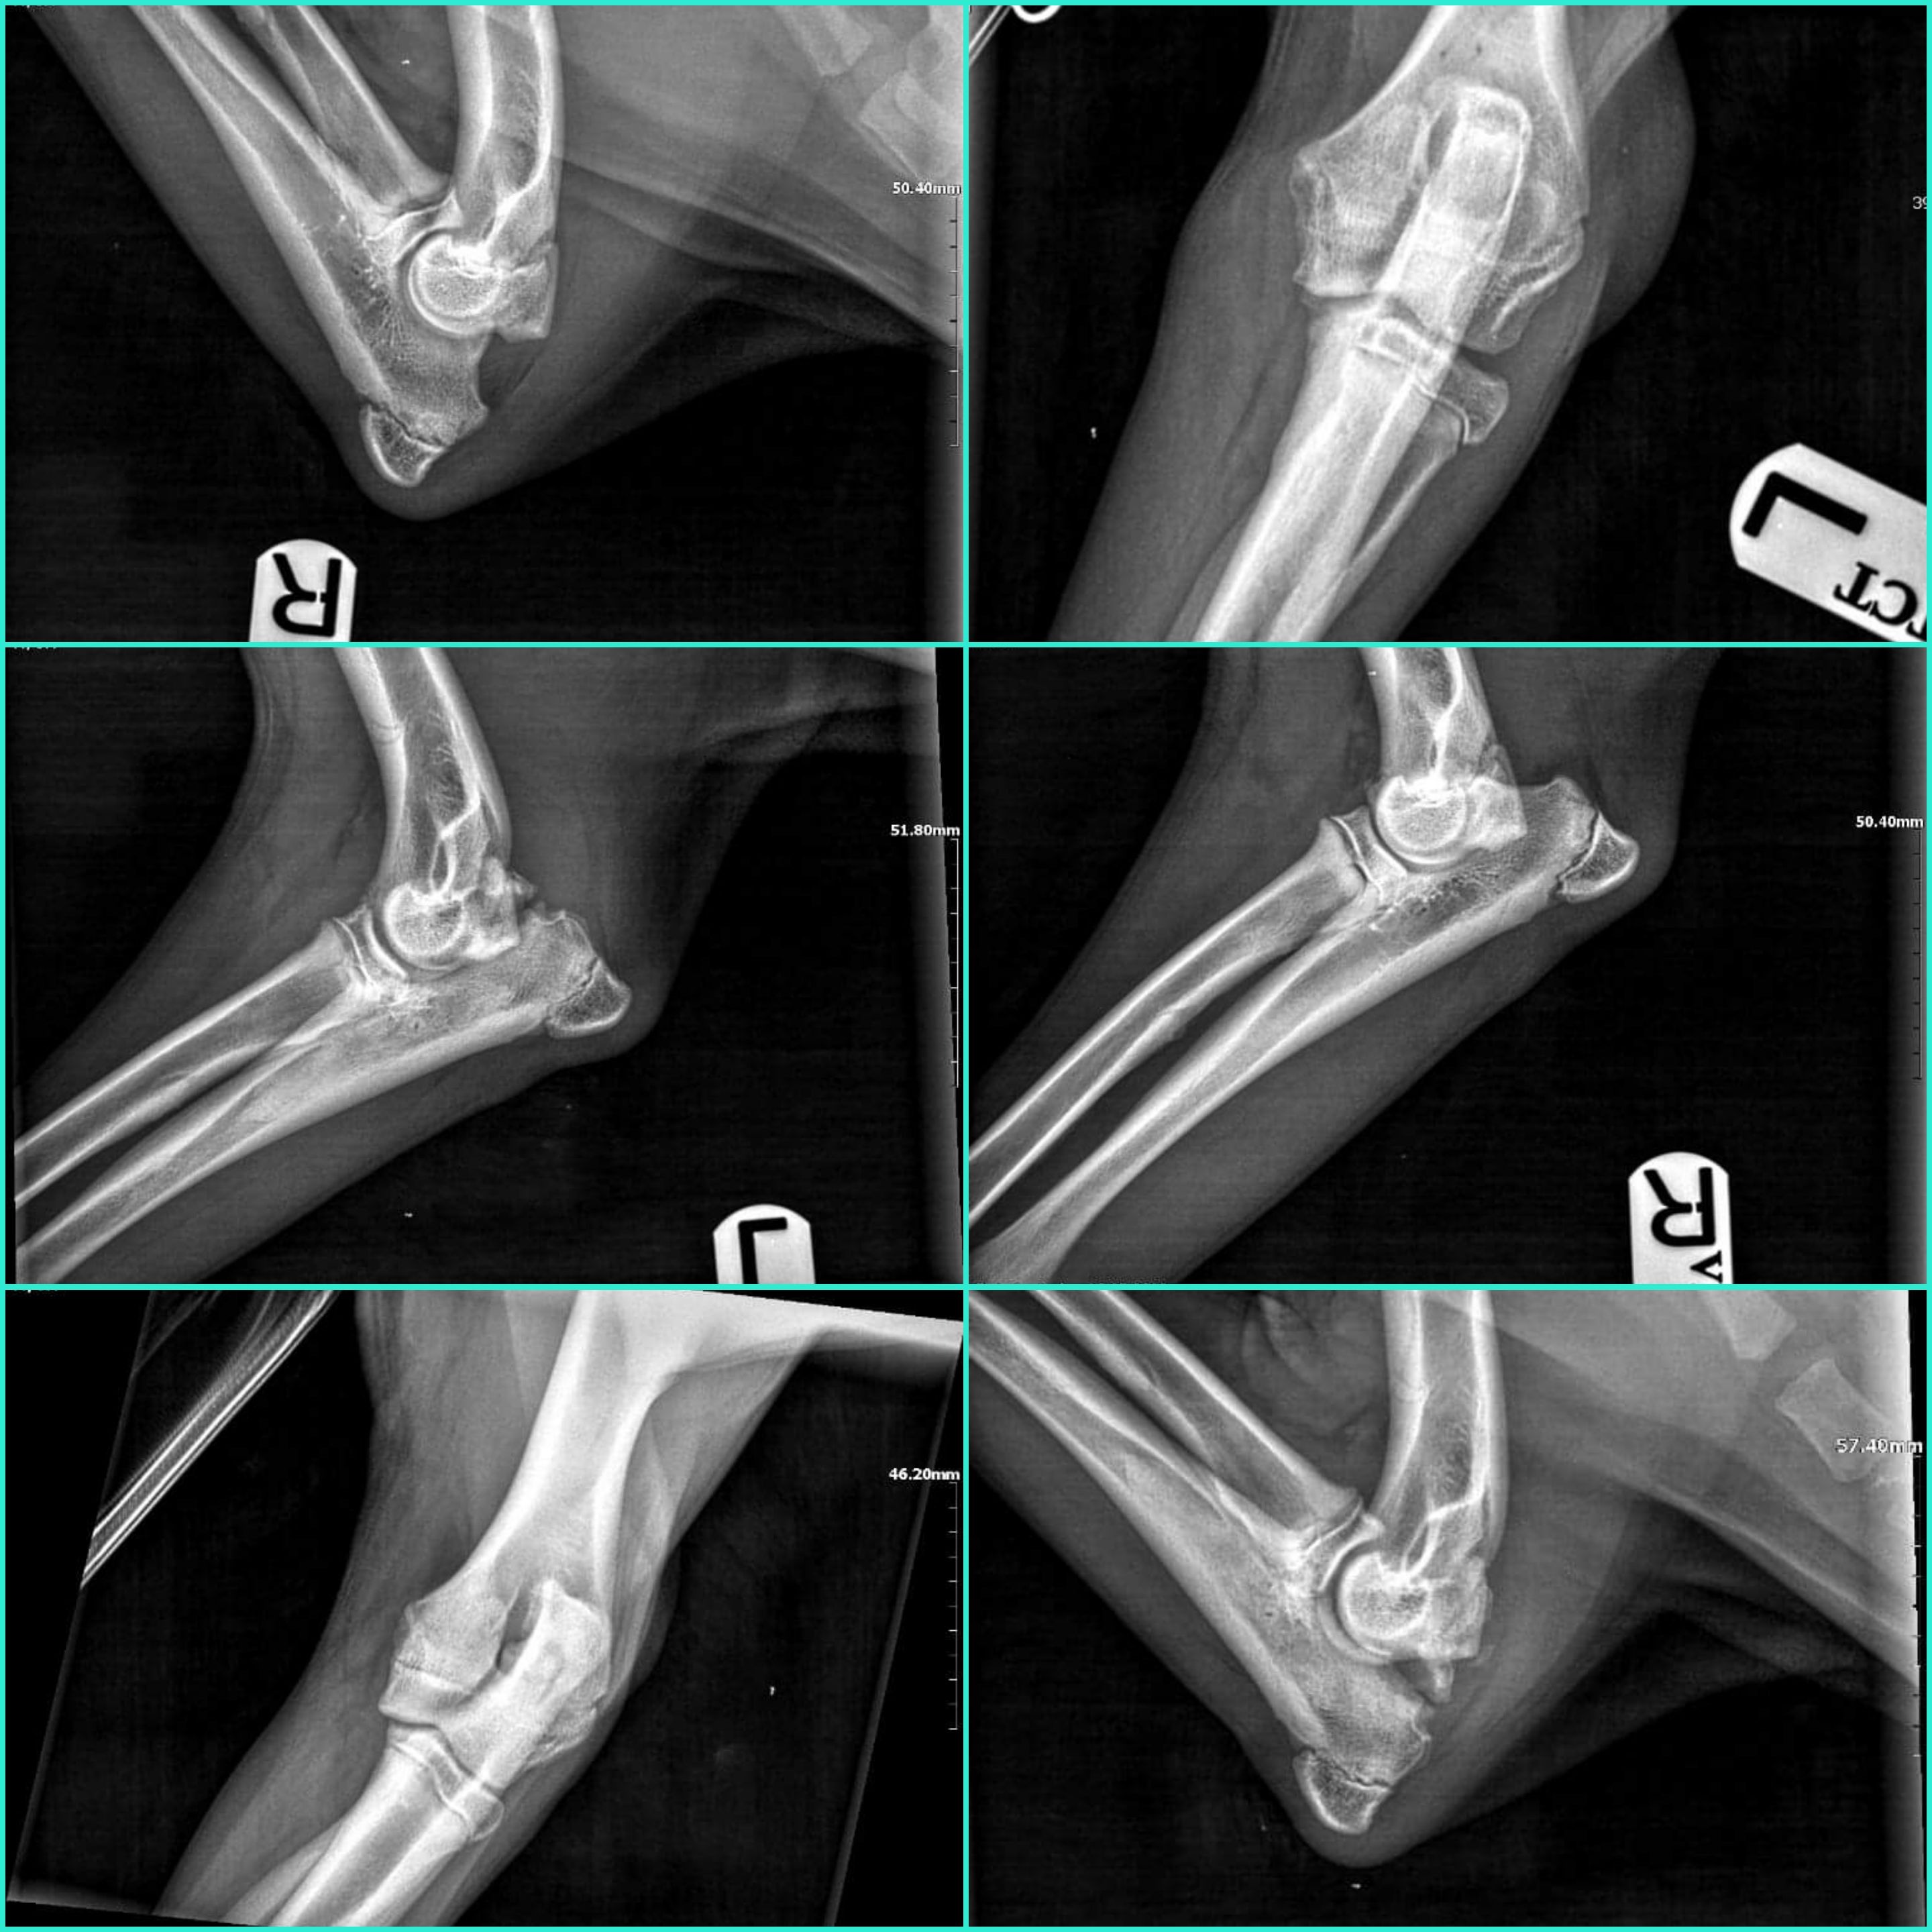

Staw łokciowy lewej nogi jest w złym stanie gdyż nie zrosła się kość, natomiast staw łokciowy prawej nogi nie jest najgorszy ale jest konieczność przeprowadzenia artroskopii obydwu stawów... Trzeba usunąć część kości która się nie zrosła.